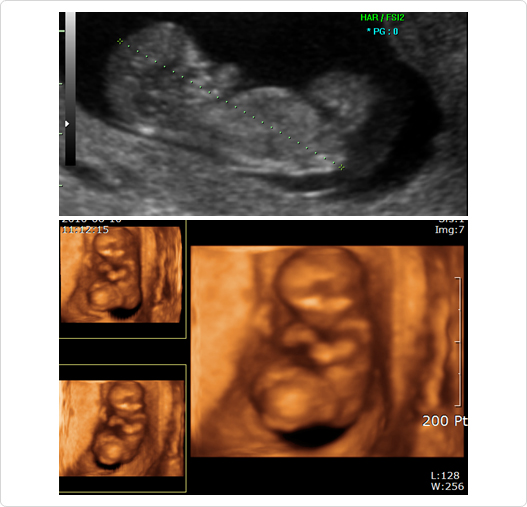

입체 초음파

- 입체 초음파는 28-30주 사이에 아이를 입체적으로 촬영하는 것입니다.